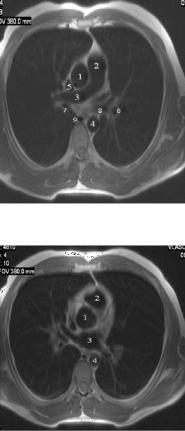

МРТ изображения органов грудной полости представлены на рисунках 13-15. МРТ Исследование грудной полости проводят с ЭКГ-синхронизацией, чтобы избежать артефактов от движения сердца и пульсации сосудов. Обычно используют импульсную последовательность спин-эхо для получения Т1взвешенных изображений. Просветы сосудов и полости сердца при этом выглядят темными за счет потери МР - сигнала от движущейся крови (времяпролетный эффект). Степень потери сигнала напрямую связана со скоростью движения.

Рис. 13. Т1-ВИ органов средостения в аксиальной проекции на уровне верхнего этажа: а – уровень пяти сосудов; б – уровень дуги аорты.

1 – правый плечеголовной венозный ствол,

2 – левый плечеголовной венозный ствол,

3 – правый плечеголовной артериальный ствол,

4 – левая общая сонная артерия,

5 – левая подключичная артерия,

6 – трахея,

7 – пищевод,

8 – дуга аорты

Рис. 14. Т1-ВИ органов средостения

в аксиальной проекции на уровне восходящей аорты: 1 – восходящая аорта,

2 – ствол легочной артерии,

3 – правая легочная артерия,

4 – нисходящая часть аорты

5 – верхняя полая вена,

6 – ветвь левой легочной артерии, 7 – просвет правого

промежуточного бронха, 8 – просвет левого верхнедолевого бронха, 9 – непарная вена